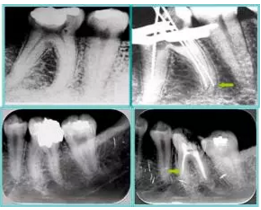

6. 術(shù)后 X 線片

術(shù)后 X 線片用來評定根管充填 長度、致密度(管壁清晰、側(cè)枝)等指標(biāo)。

圖為根管充填術(shù)后 X 線片。圖中可見,根管充填較好。右下圖有白色小點(diǎn),為側(cè)方加壓導(dǎo)致糊劑擠出所致,表明根管充填比較致密。

致密、恰到好處的充填可去除干凈根管里感染灶,機(jī)體逐漸恢復(fù)。

多根牙時候需進(jìn)行偏移投照,正位投照無法說明具體哪根牙根管充填效果。